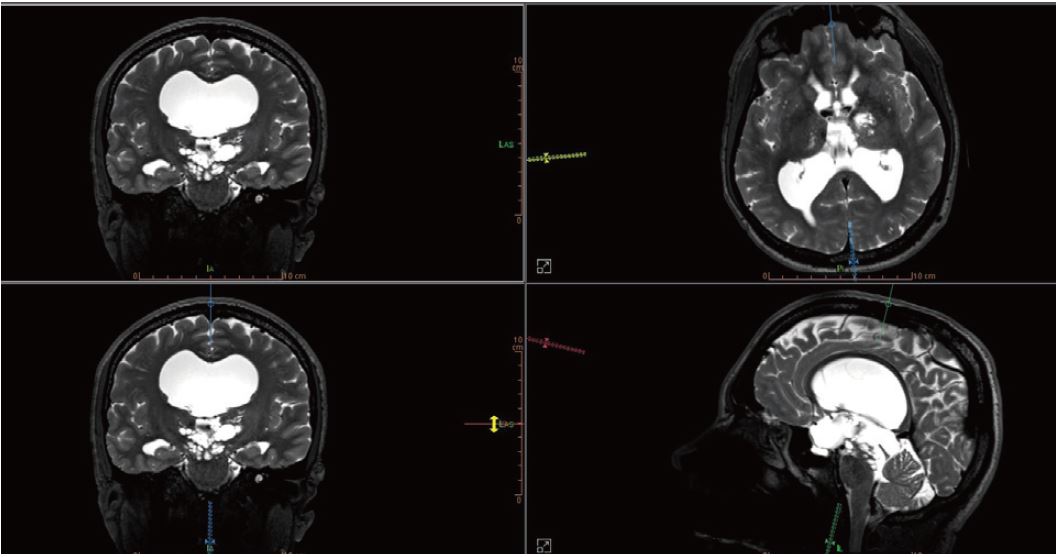

Розширення Вірховського та Робінового просторів (рис. 1) є доброякісною патологією. У більшості випадків захворювання протікає безсимптомно. Контрастне посилення просторів Вірхова і Робіна спостерігається при багатьох різних патологіях. Розширення простору Вірхова і Робіна менше 2 мм можуть спостерігатись в будь-якому віці. Розширення більше 2 мм набагато частіше зустрічаються у людей похилого віку.

Рисунок 1

Простори Вірхова і Робіна або периваскулярні простори - це простори, що оточують перфорантні кровоносні судини (артерії, артеріоли, вени та венули), які входять у мозок. Простір Вірхова і Робіна — це простори різного розміру, заповнені інтерстиціальною рідиною  (також називається інтерстицієм, рідиною, яка заповнює простір між кровоносними капілярами та клітинами). Вони вкриті м’якою інтимою, яка є безсудинним шаром м’якої оболонки (однієї з трьох оболонок, що утворюють мозкову оболонку), і супроводжує проникнення перфорантних артерій у мозкову паренхіму.

Патофізіологія розширення просторів Вірхова і Робіна вивчена погано. Розглянуто кілька причин, у тому числі: підвищена проникність судин, аномалія дренажу інтерстиціальної рідини, атрофія паренхіми або фіброз і обструкція просторів Вірхова і Робіна. Поширеність і розмір розширених просторів Вірхова і Робіна зростає з віком, але патологічне значення розширення простору залишається невизначеним.

Простори Вірхова та Робіна стають більш видимими на зображеннях завдяки постійному вдосконаленню просторової роздільної здатності. Розширення периваскулярного простору Вірхова-Робіна є частим явищем і все частіше зустрічається завдяки прогресу в нейровізуалізації.

Програма перегляду на робочій станції забезпечує хорошу візуалізацію та аналіз розширень простору Вірхова та Робіна з ізотропної послідовності FSE T2, отриманої в трьох площинах, а також візуалізацію гідроцефалії (рис. 2). Інструменти MPR (багатопланарна реконструкція) та MIP (проекція максимальної інтенсивності), які також доступні на робочій станції, допомагають при перегляді та аналізі зображень.

Рисунок 2